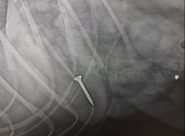

Wurstel con vite in piazza Cavour:

cagnolina cade nella trappola

ANCONA – L’animale è stato portato dalla sua proprietaria in una clinica per rimuovere il corpo estraneo. La veterinaria Chiara Bertani: «Al momento consiglio di tenere il guinzaglio sempre corto, evitare le aiuole o gli anfratti dato che è proprio lì che vengono gettate le esche e, per quei cani particolarmente golosi, fargli indossare la museruola durante le passeggiate»